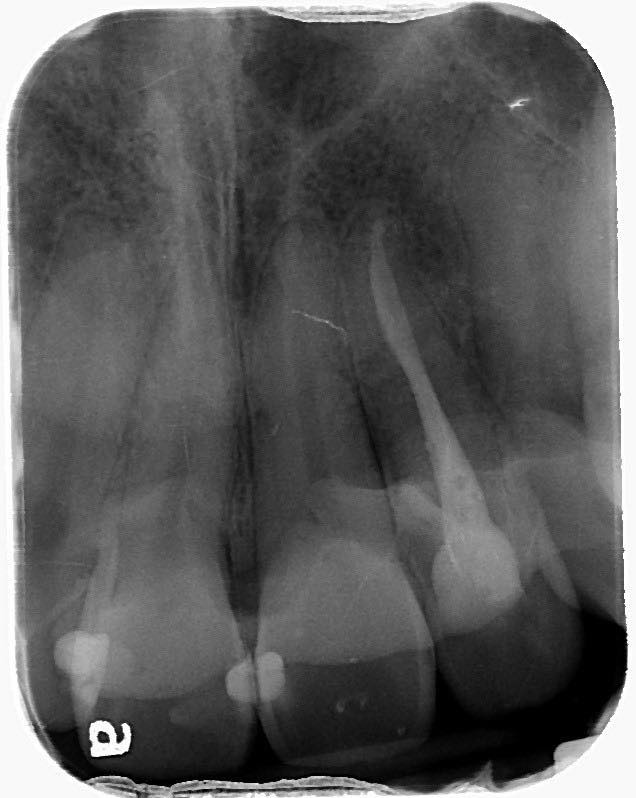

Treatment of the palato-radicular groove and cemental tear: a case report

Deep probing depth and CT scan can be done to diagnose the periodontal disease and cemental tears. Open flap surgery to remove tears of cementum and composite resin fills the groove. Then, GTR with FDBA and collagen membrane.

右上側門牙經由牙周再生手術,誘導牙周細胞的再生,修復先前受損的牙周組織。

GTR: Tetracycline + NS, Gentamicin irrigation, BioOss(s) + Lyoplant